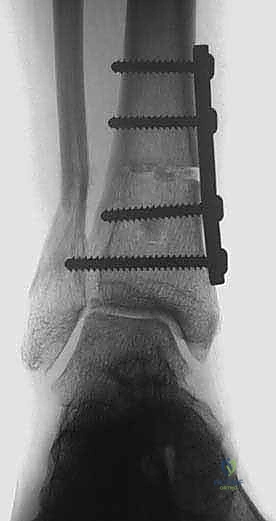

| قطع العظم فوق الكاحل (Osteotomy) | قطع عظم الساق وإعادة توجيهه لتصحيح المحور وتوزيع الحمل على الغضروف السليم. | يحافظ على المفصل الطبيعي، يحافظ على الحركة، يوقف تدهور الخشونة، لا يمنع إجراء الدمج أو الاستبدال في المستقبل إذا لزم الأمر. | يتطلب فترة تعافي أطول لالتئام العظم، يتطلب مهارة جراحية فائقة جداً. | المرضى الأصغر سناً، النشطين، ذوي الخشونة المتركزة في جانب واحد (التقوسية)، مع وجود غضروف سليم في الجانب الآخر. |

بناءً على هذا التحليل، تعتبر جراحة قطع عظم الساق فوق الكاحل هي الخيار الذهبي للمرضى النشطين والشباب نسبياً الذين يعانون من خشونة غير متكافئة (متركزة في الجانب الداخلي).

التخطيط الجراحي: دقة المليمتر مع الدكتور محمد هطيف

النجاح في جراحة قطع العظم لا يحدث في غرفة العمليات، بل في مرحلة التخطيط التي تسبقها. يستخدم الدكتور هطيف برمجيات حاسوبية متقدمة لتحليل صور الأشعة وحساب زوايا التصحيح المطلوبة بدقة متناهية.